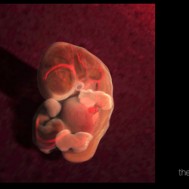

Baby: Week 6

You’re now making spontaneous movements, and can twitch your trunk and limb buds

Each day, changes make you more recognisable as a small person just like you. Now your lungs are forming![1] Brain function, as measured by EEG waves, can be recorded within days.[2] Nerve cells in the brain are connecting, forming primitive neural pathways. Your hands can bend at the wrist, and webbing is disappearing from your feet. Your tail is just about gone. Tastebuds are forming on your tongue.[3] You’re now making spontaneous movements, and can twitch your trunk and limb buds.[4]